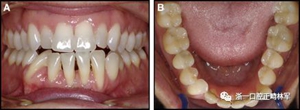

相鄰切牙之間的轉(zhuǎn)矩差異很可能與較小直徑的柔性螺旋弓絲有關(guān)(圖7),但這些也可能在極軟弓絲上發(fā)生(圖8)。在某些情況下,牙齒移動嚴(yán)重到足以導(dǎo)致牙周損傷(圖9)。我們沒有觀察到在僅固定在尖牙上的較大直徑的尖牙到尖牙的弓絲上的相鄰切牙之間扭矩差異的例子。

圖7.左右切牙扭矩不一致的柔性螺旋弓絲保持器:A,正面視圖; B,咬合面視圖。 下頜左側(cè)尖牙的唇側(cè)移位:C和D,頰面視圖(Anne-Marie Renkema博士提供)。